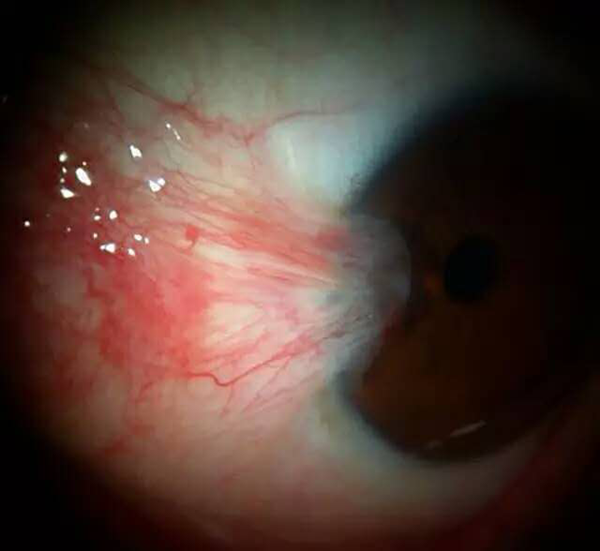

胬肉一般发生于眼睛表面,常由睑裂部球结膜向角膜方向发展,由于形状与昆虫的翅膀相似,因此被称为翼状胬肉。

翼状胬肉需要根据其发展情况来决定是否需要手术治疗,一般位于静止期时,胬肉的头部扁平,体部补充血,表面光滑,如果此时的胬肉较小且不影响视力,可以以观察为主。如果是位于进行期且对视力有影响,引起散光、视力下降等问题,则需要根据实际情况考虑是否手术。